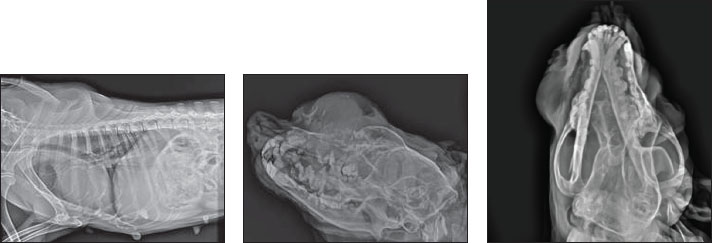

The radiology displayed an osteolytic expansile lesion, proliferative periosteal reaction, irregular margin, and stippled to speculated columnar periosteal reaction (Fig. 3). The tumor originated from the end of the nostrils to the ocular region. The transition zone is poorly demarcated from normal bone.

Fig. 3. X-ray showing osteolytic expansile lesion proliferative periosteal reaction irregular margin and stippled to speculated columnar periosteal reaction.

The frontal bone, nasal bone, and maxilla depicted gross destruction. These are features of aggressive bone lesions. The differential diagnosis included multiple myeloma, Osteoma, Squamous cell carcinoma, malignant melanoma, acanthomatous ameloblastoma, and fibrosarcoma.